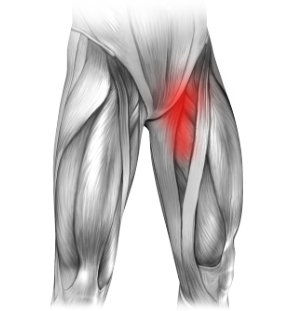

Przyczepy i mięśnie

Pachwina jest miejscem przyczepu wielu mięśni i więzadeł. Ich nadmierne przeciążenie może prowadzić do ich uszkodzenia. Ból w lewej pachwinie promieniujący na nogę często pojawia się u sportowców i jest wynikiem uszkodzenia mięśni (zwłaszcza przywodzicieli), bądź przyczepiających się do kości ścięgien i więzadeł.

Do diagnozy najczęściej wystarczy badanie przez doświadczonego lekarza, który w uzasadnionych przypadkach może posłużyć się USG.

Leczenie z reguły polega na odpoczynku oraz schładzaniu miejsca uszkodzenia. Czasami jednak konieczne jest wykonanie specjalnych zastrzyków, które mogą zmniejszać zapalenie lub/i przyśpieszać regenerację. Fizjoterapia również często może pomóc w leczeniu takiego bólu.